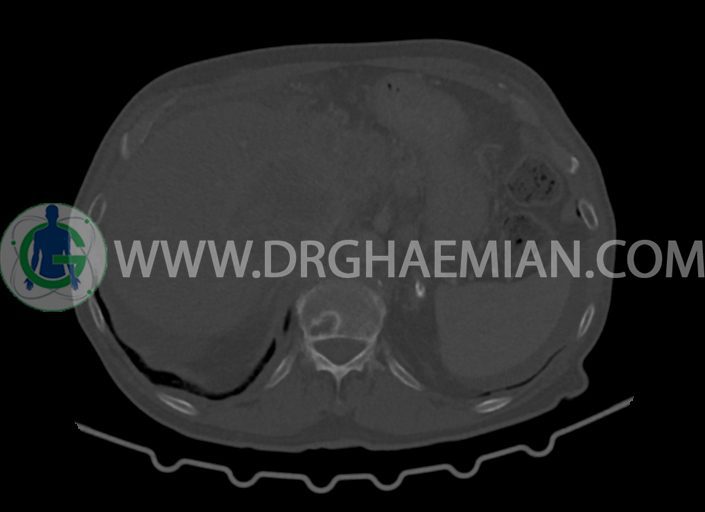

در سی تی اسکن اسپیرال شکم و لگن با کنتراست خوراکی و وریدی (مولتی دیدکتور 16 با مقاطع ظریف و بازسازی های ساژیتال و کرونال) :

-مایع آسیت با حجم Mild در ساب فرنیک دو طرف ، ساب هپاتیک و ساب اسپلنیک و اینترلوپ لگنپ

-توده ی بزرگ با حدود لبوله به ابعاد 89x87x76mm در لوب چپ کبد همراه با گسترش اکستراکپسولار و

شواهد آتروفی لوب جپ کبد

-توده به قطر 33mm در سگمان 6 کبد

-توده ی هیپودنس به ابعاد 30x21mm در ورید پورت خارج کبدی مطرح کننده ی Tumor thrombosis

در ارتباط با ضایعات کبدی در درجه ی اول متاستاز مطرح است. در تشخیص افتراقی با توجه به آتروفی لوب

چپ، mass forming cholangiocarcinoma نیز مطرح می گردد.